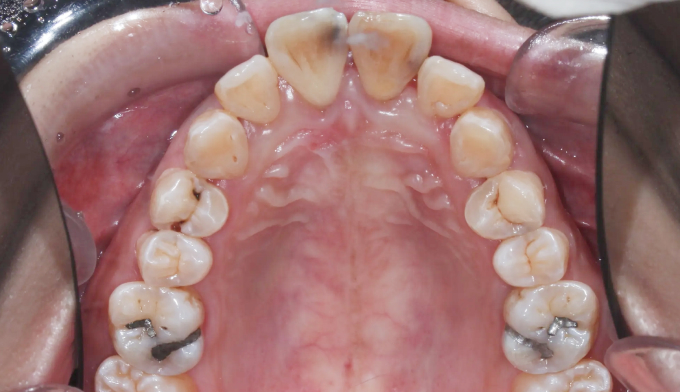

뻐드러진 앞니로 인한 돌출입과, 구강위생관리 부족으로 인한 다수의 충치가 관찰된 케이스입니다.

교정시작 전 충치가 많은 분들은 교정치료과정에서 더 많은 충치가 생길 가능성이 매우 높기 때문에 먼저 양치질교육을 비롯한 전반적인 구강위생교육이 이루어져야 합니다. 그리고 급한 충치를 먼저 치료하고 교정치료에 들어갑니다.

충치가 진행된 부분이 워낙 광범위하고 많아, 무리해서 치아를 전부 치료하지 않았습니다. 최소한으로 치료하고 지켜보기로 하였습니다.